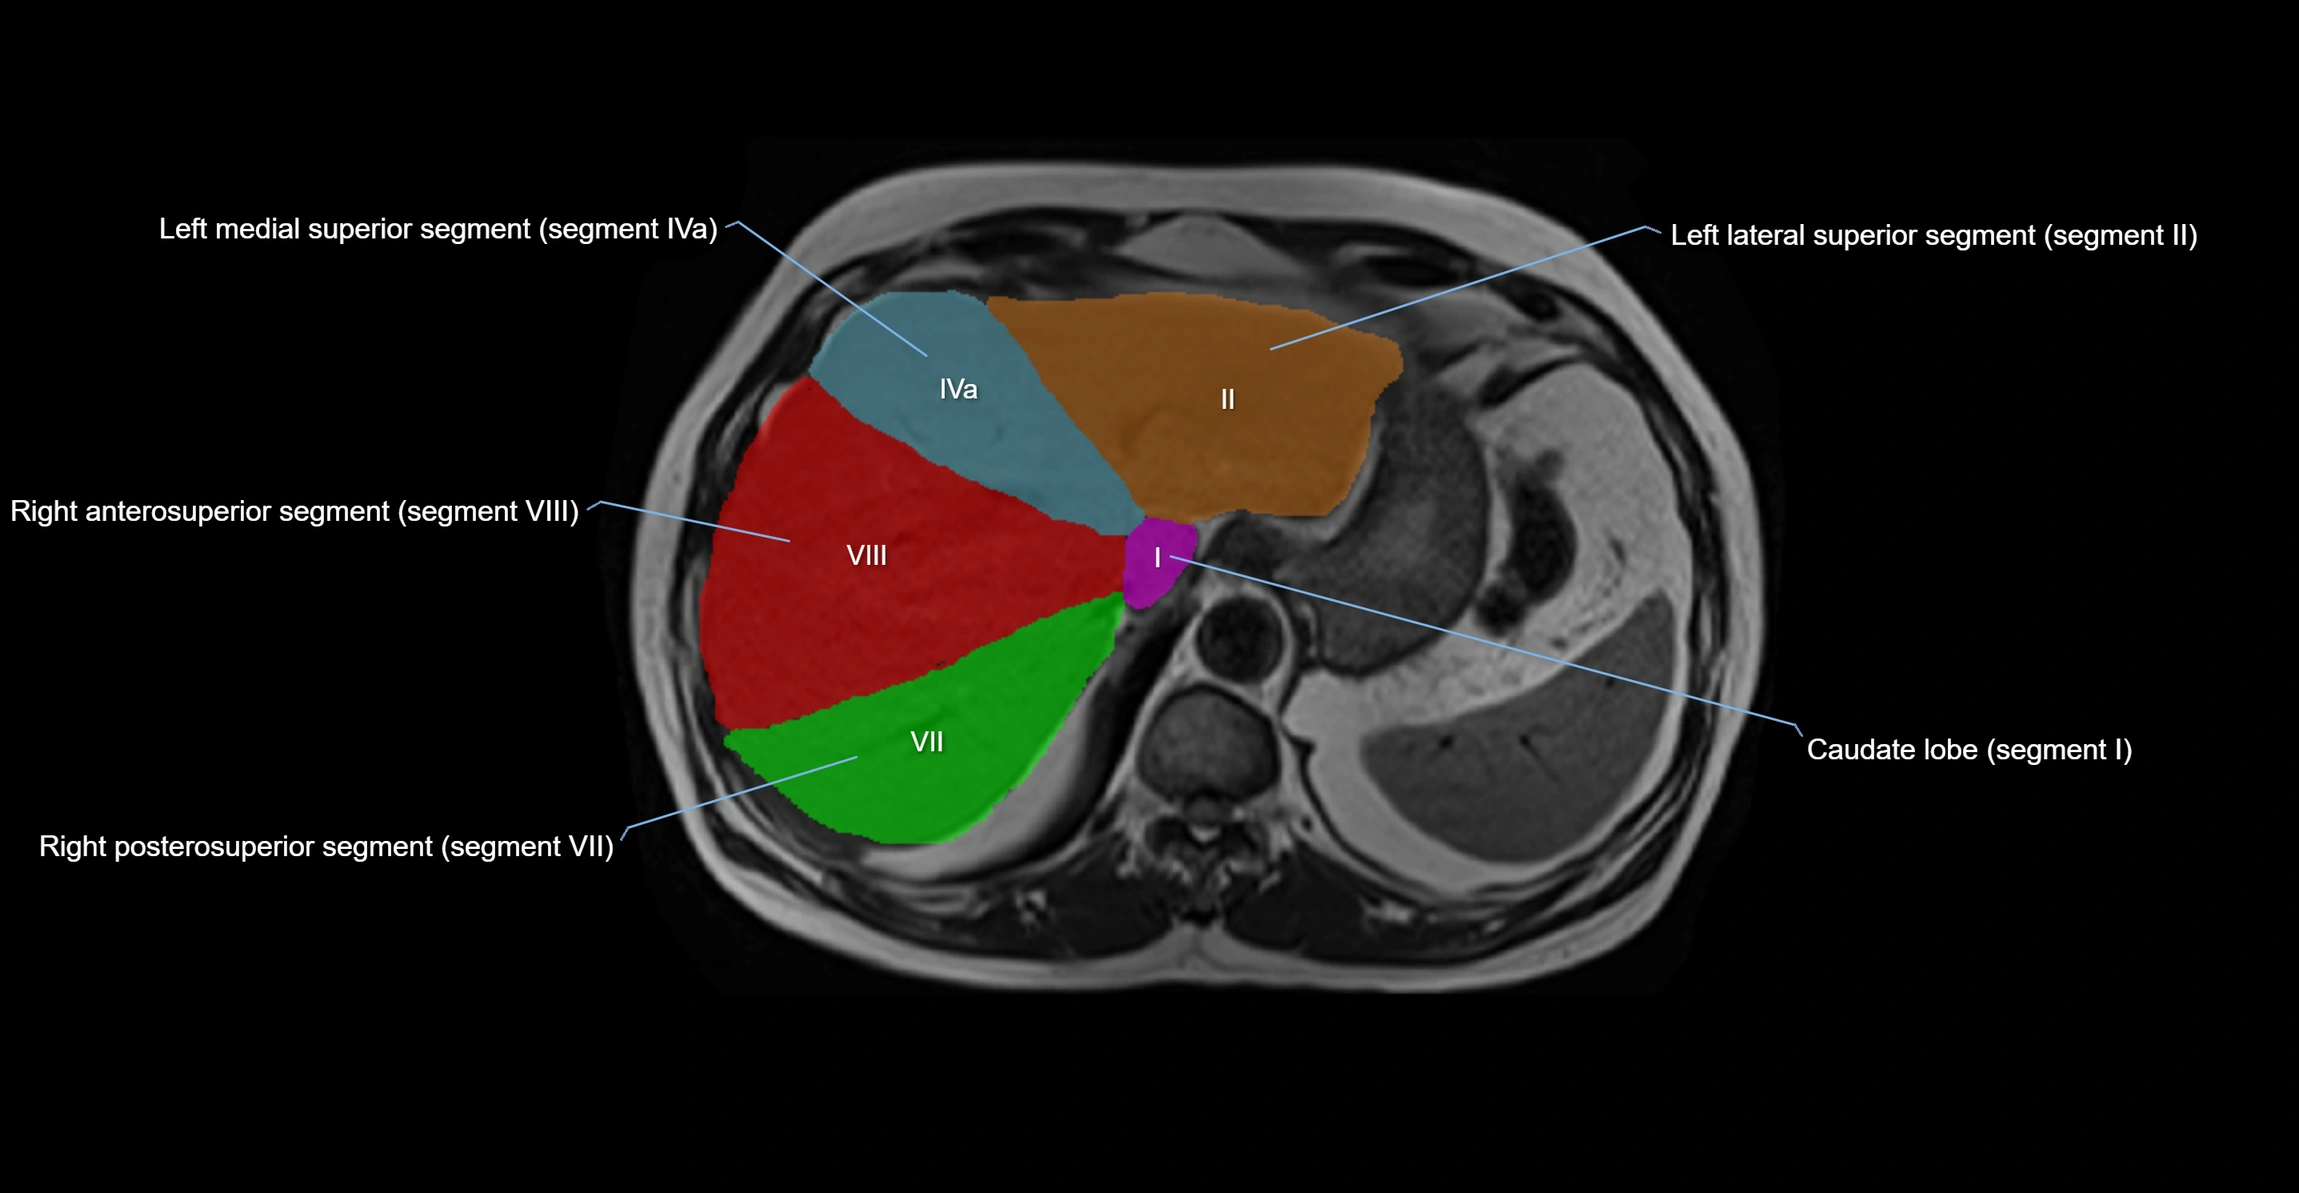

The caudate lobe of the liver is a distinct anatomical subdivision of the liver, designated as segment I in Couinaud’s classification. It lies on the posterior surface of the liver, between the fissure for the ligamentum venosum (left boundary) and the groove for the inferior vena cava (IVC) (right boundary). Superiorly, it is related to the posterior liver surface, and inferiorly it is separated from the left lobe by the porta hepatis.

The caudate lobe is unique because it receives dual portal venous and arterial inflow from both the right and left portal veins and hepatic arteries. It also has independent venous drainage directly into the IVC via multiple small hepatic veins, unlike other lobes that drain through the three main hepatic veins.

This anatomical autonomy makes the caudate lobe especially significant in liver surgery, transplantation, and hepatic venous outflow obstruction syndromes (e.g., Budd–Chiari syndrome). Enlargement of the caudate lobe is a characteristic imaging feature in chronic liver disease and cirrhosis.